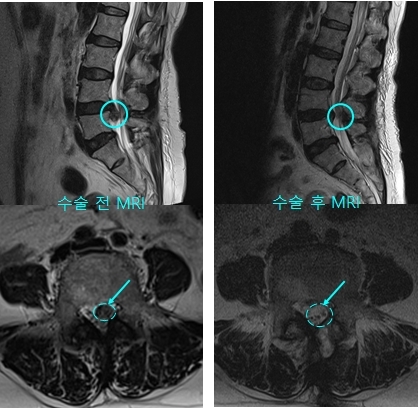

이재원 교수는 “위 환자의 사례처럼 디스크가 크고 하방 전위가 심할 경우 기존의 절개디스크절제술로 수술하게 되면 절개를 많이 해야 할 뿐 아니라 디스크 제거를 위해 뼈를 제거해야 하는 범위도 넓어지게 된다. 하지만 내시경 수술법을 이용하면 뼈를 제거하는 범위를 최소화하고 깊숙한 부분까지 모두 직접 확인하면서 깨끗이 제거할 수 있다”고 했다.